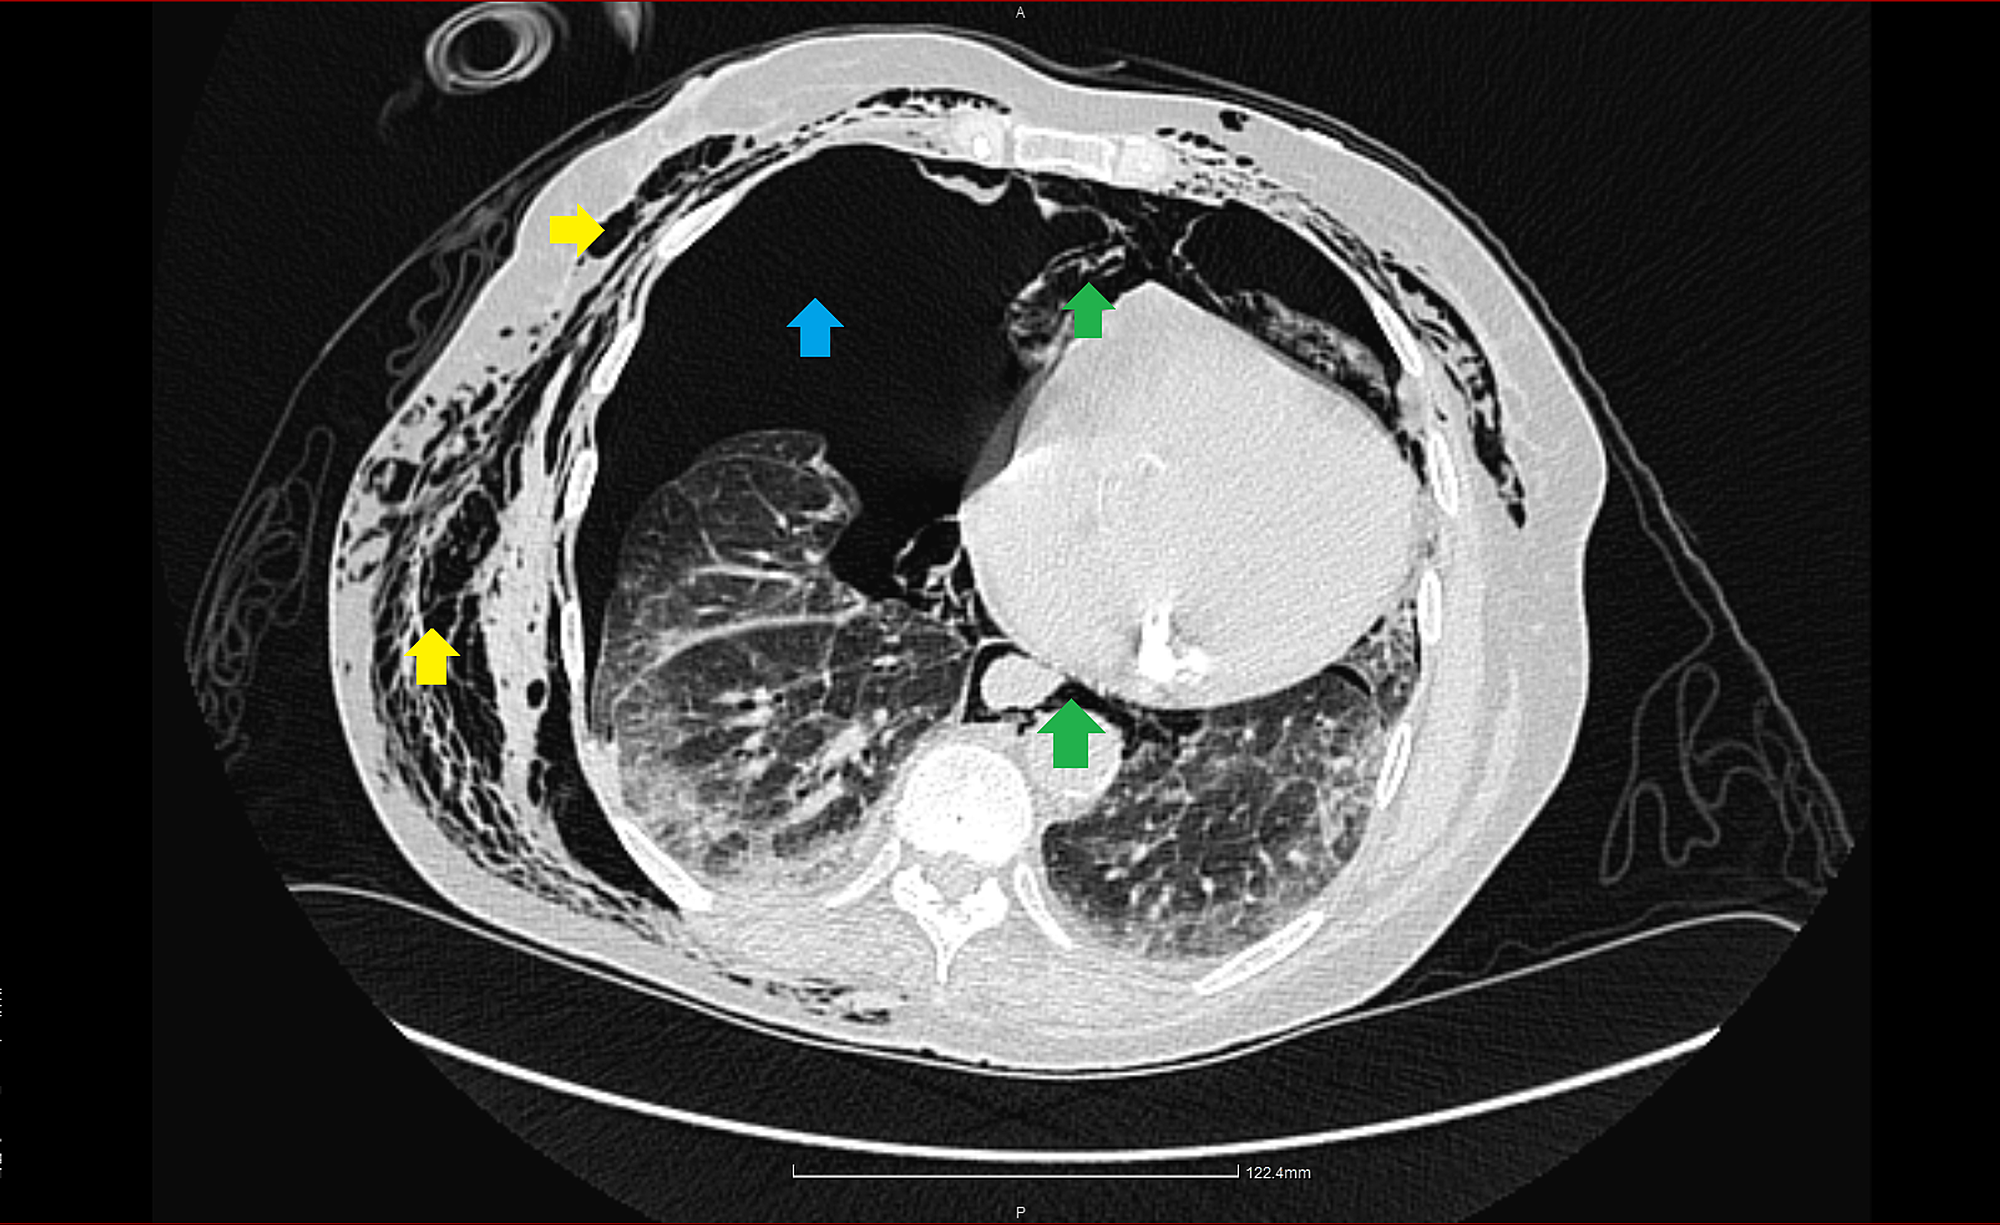

Tension Pneumothorax Ct. A subsequent thoracotomy was performed, during which tearing of a large branch of the. Large right pneumothorax, with a markedly hyperlucent right hemithorax as a result.

A lung ct scan uncovered that a tension pneumothorax has been developed (figure 2). Gas in the pleural space is termed a pneumothorax.

Tension pneumothorax Radiology at St. Vincent's University Hospital, Tension pneumothorax is accumulation of air in the pleural space under pressure, compressing the lungs and decreasing venous return to the heart.

Chest CT scan uncovered a tension pneumothorax Download Scientific, A tension pneumothorax, when intrapleural pressure exceeds atmospheric pressure throughout expiration, is a medical emergency that requires immediate.

Left tension pneumothorax Image, Tension pneumothorax may occur after spontaneous pneumothorax, although it is more common after traumatic pneumothorax or with mechanical ventilation.

Cureus A Case of Tension Pneumothorax After Diverticular Rupture, Tension pneumothorax occurs when pleural pressure is transmitted to the mediastinum (see image.

Tension pneumothorax, CT scan Stock Image C058/2881 Science Photo, Clinical signs of a tension pneumothorax include tachypnea, hypotension, pleuritic chest pain, tracheal deviation, jugular vein distention, and unilateral absence of breath sounds.

Thoracic CT scan on admission. Leftsided tension pneumothorax with, Tension pneumothorax is accumulation of air in the pleural space under pressure, compressing the lungs and decreasing venous return to the heart.